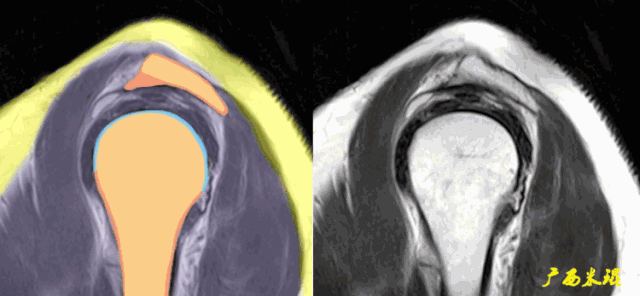

肩关节MRI检查扫描平面

(1)斜冠状位:平行于冈上肌腱长轴,主要评估冈上肌。

(2)斜矢状位:垂直于冈上肌长轴,观察肩峰形态及喙肩弓,观察肩袖4个组分的短轴断面。

(3)平行于关节盂/垂直于盂肱关节,主要评估盂唇,同时兼顾肩胛下肌、冈下肌及小圆肌。

肩关节MRI检查序列

1.T1WI:清楚显示解剖结构。

2.T2WI:显示病灶部位及大小有一定优势,但对于退变的诊断,容易受到脂肪的干扰。

3.PDFS:减少脂肪信号的干扰,增加病变内水分子的信号显示,能更好反映肩袖细微解剖变化。

正常肩袖的MRI表现

各个序列肩袖均表现为均匀的低信号,是肌腱的延续。